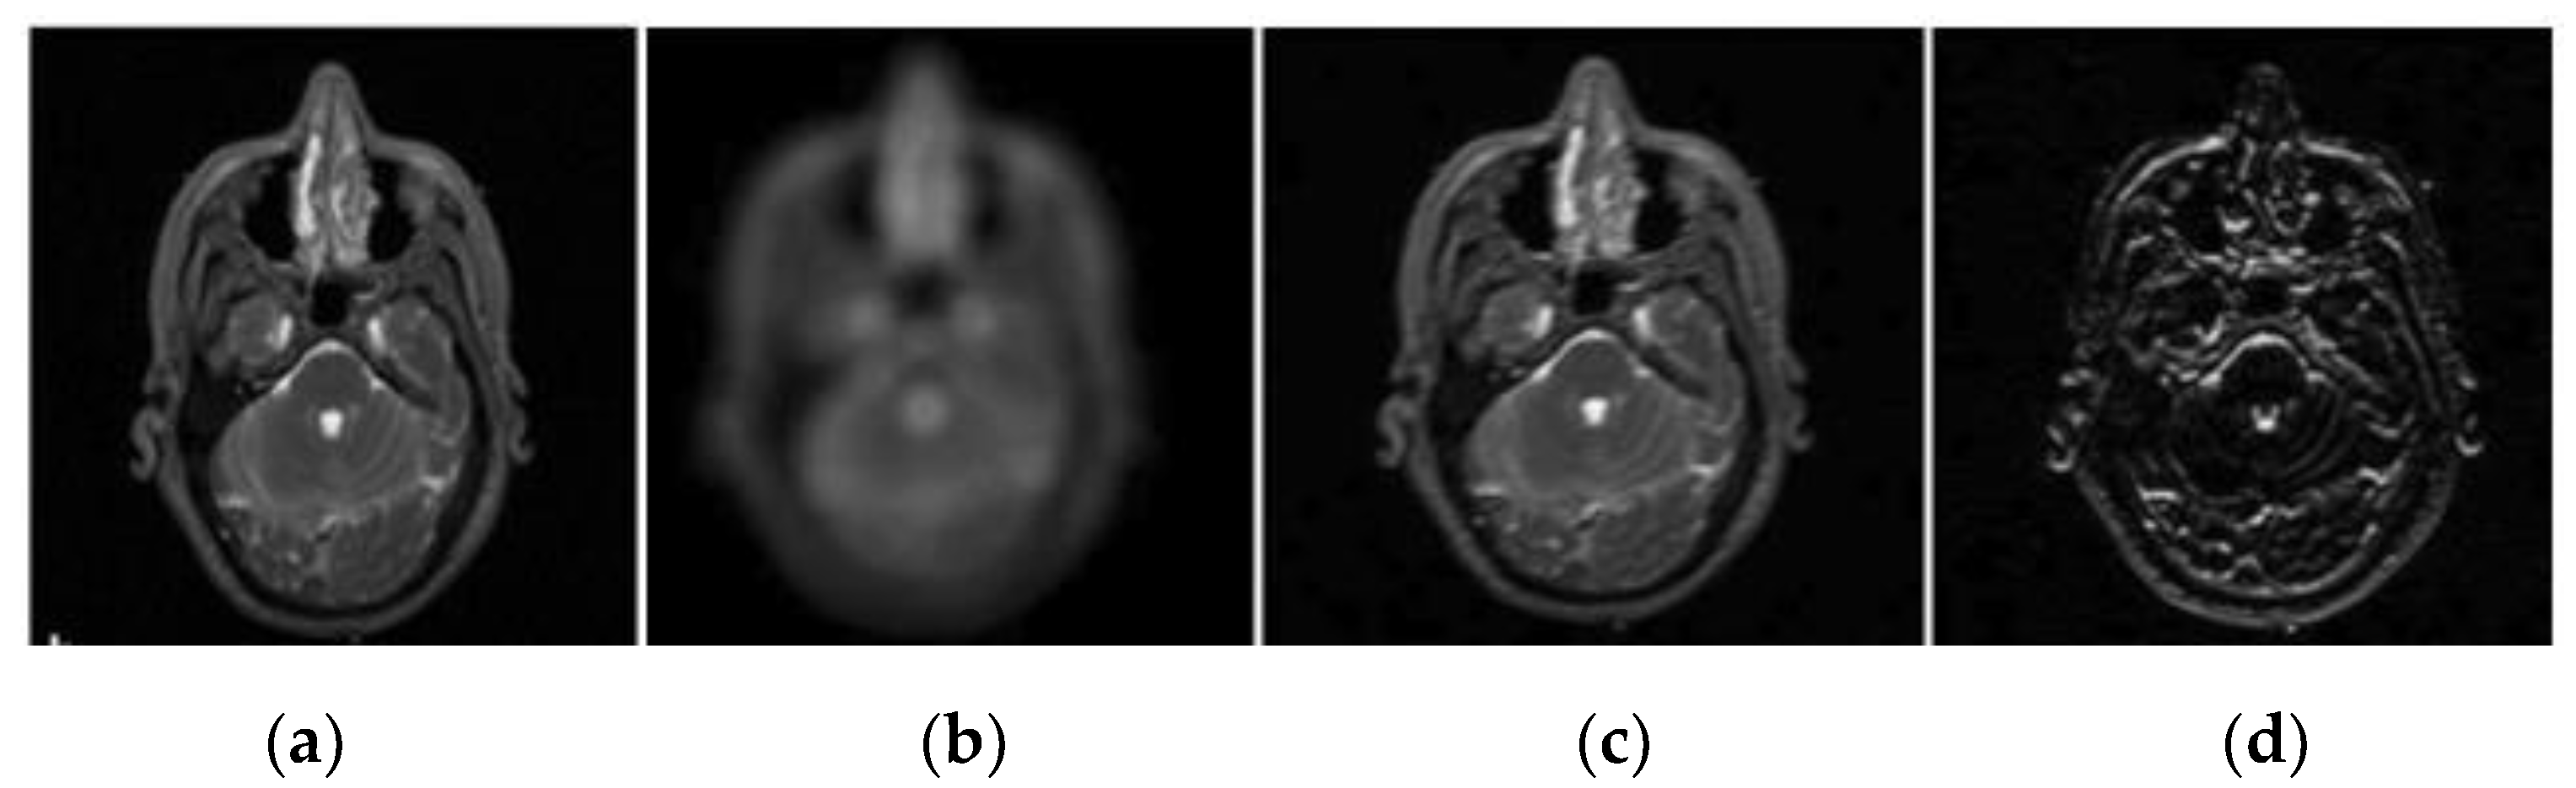

2.1. Pre-Processing

2.2. Wavelet Decomposition

2.3. Generation of Saliency Maps

2.3.2. Bottom-Up Saliency Maps (

Elliptical Local Binary Pattern

2.3.3. Final Saliency Map